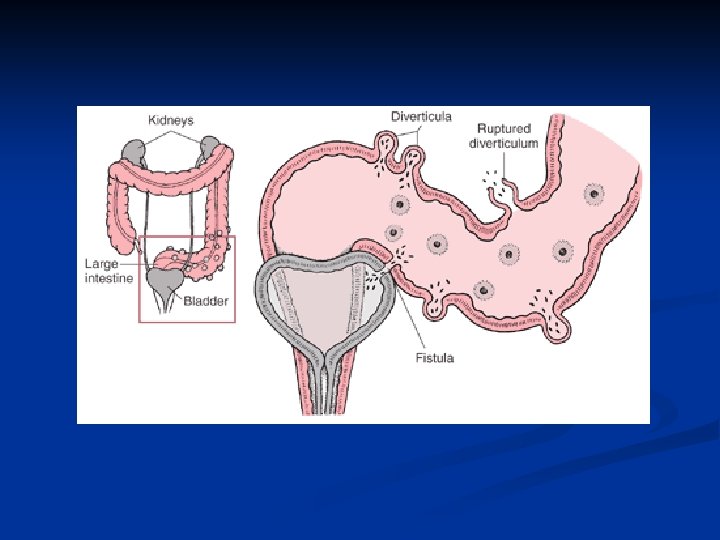

Diverticulosis of the Colon IV. Complications: n n n inflammation ( diverticulitis ) perforation bleeding postinflammatory stenosis obstruction fistula with the surrounding organs ( urinary bladder, vagina )

Diverticulosis of the Colon V. Treatment antibiotics, bed rest, liquid diet, spasmolytics ( acute attack of diverticulitis ) operation – 10% patients require operation one stage resection two stage procedures - colostomy - exteriorisation of the affected bowel - Hartman´s procedure - fistulas – resection of the bowel and closure of the fistula